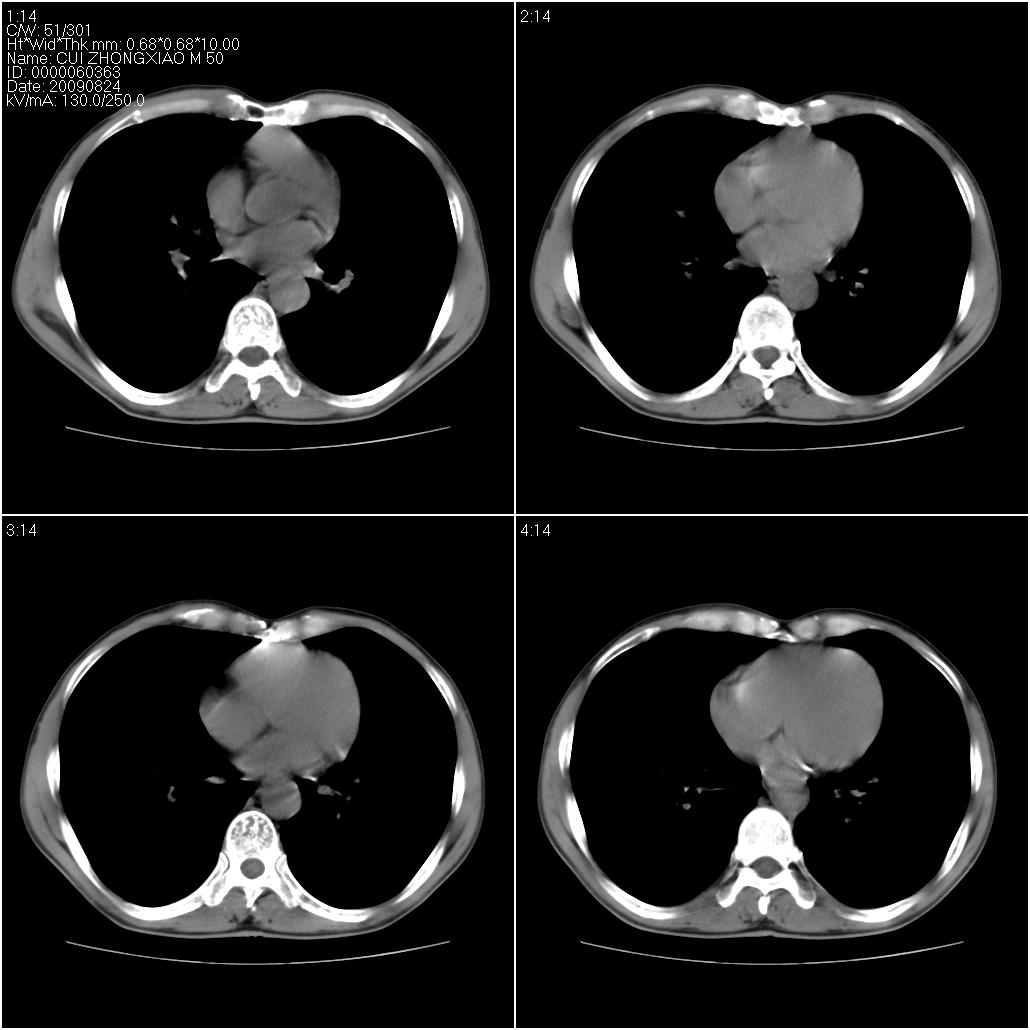

标题: CT21851:男性,50岁。间断性咳嗽半年。 [打印本页]

标题: CT21851:男性,50岁。间断性咳嗽半年。

磨玻璃样改变(左肺及右肺上叶前段),边缘模糊,考虑炎症,建议严格抗炎治疗后复查除外肺泡蛋白沉积症或肺泡出血(病人有咯血吗) 肺泡癌.

肝左叶肝内胆管扩张,进一步检查.

双肺磨玻璃征改变。。。支持楼上